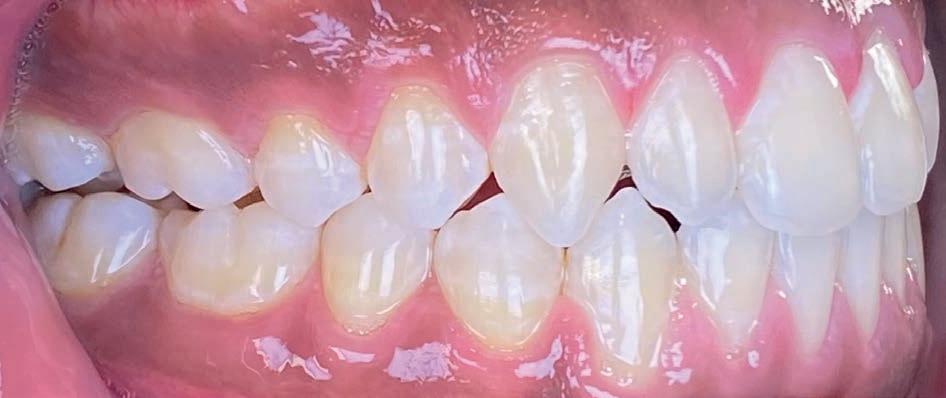

Casus in Proces

Patiënt Sonnie presenteerde zich met ernstig ruimtegebrek ter hoogte van de 13 en 44 en een kruisbeet aan de zijde van de 15 en 14. De 13 was ectostematisch gepositioneerd, waardoor extractie aanvankelijk als mogelijke behandeloptie werd overwogen.

Door een combinatie van verbreding en het inzetten van een D-gainer wordt de benodigde ruimte gecreeerd om alle elementen correct in de tandboog te positioneren, waardoor extracties kunnen worden vermeden. De behandeling zal binnen twee jaar worden afgerond; het eindresultaat wordt gedeeld in editie 2 van ons magazine.

Start behandeling

Midden behandeling

Laatste fase